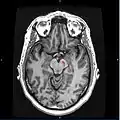

Section through superior colliculus showing Substantia nigra.